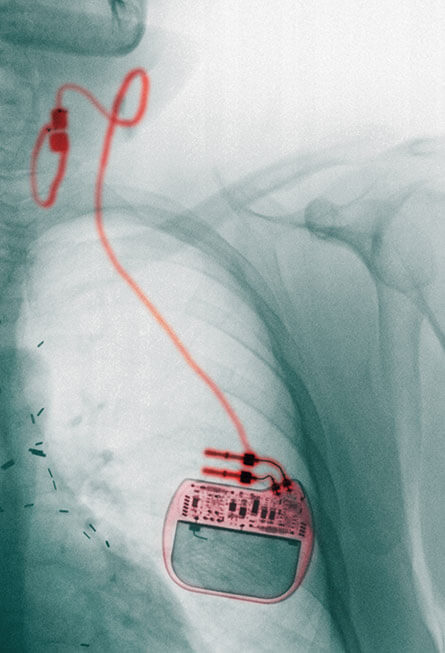

The US FDA has already approved using Electrical Stimulation of the Vagus nerve through implants within the patient’s body to treat epilepsy and unmitigable depression which pharmaceutical medicine can’t help.

As I wrote earlier, implants have already been approved a while back by the FDA. But now the geeks are working on nerve stimulation which works non-invasively from outside the body. Like a watch or bluetooth headset that by-the-way keeps headaches away :) There are of course a few side effects and HUGE risks, but most current studies show stuff like hoarseness, neck pain and coughing which goes away when treatment is stopped. I read about this on Viva vagus: Wandering nerve could lead to range of therapies.